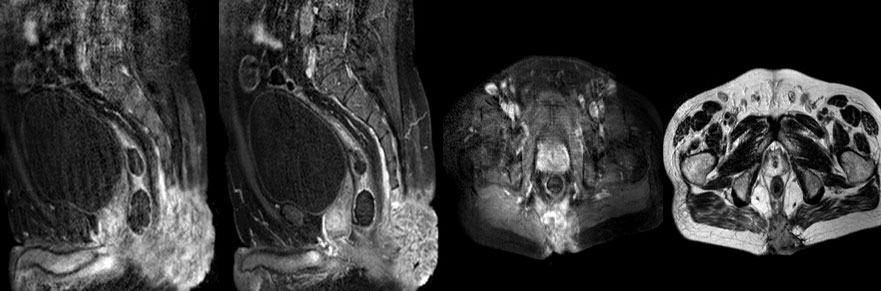

Ameliyat öncesi: MR’da kuyruk sookumunu etkileyen ve cilde uzanan düzensiz sınırlı tümör dokusu görülmekte